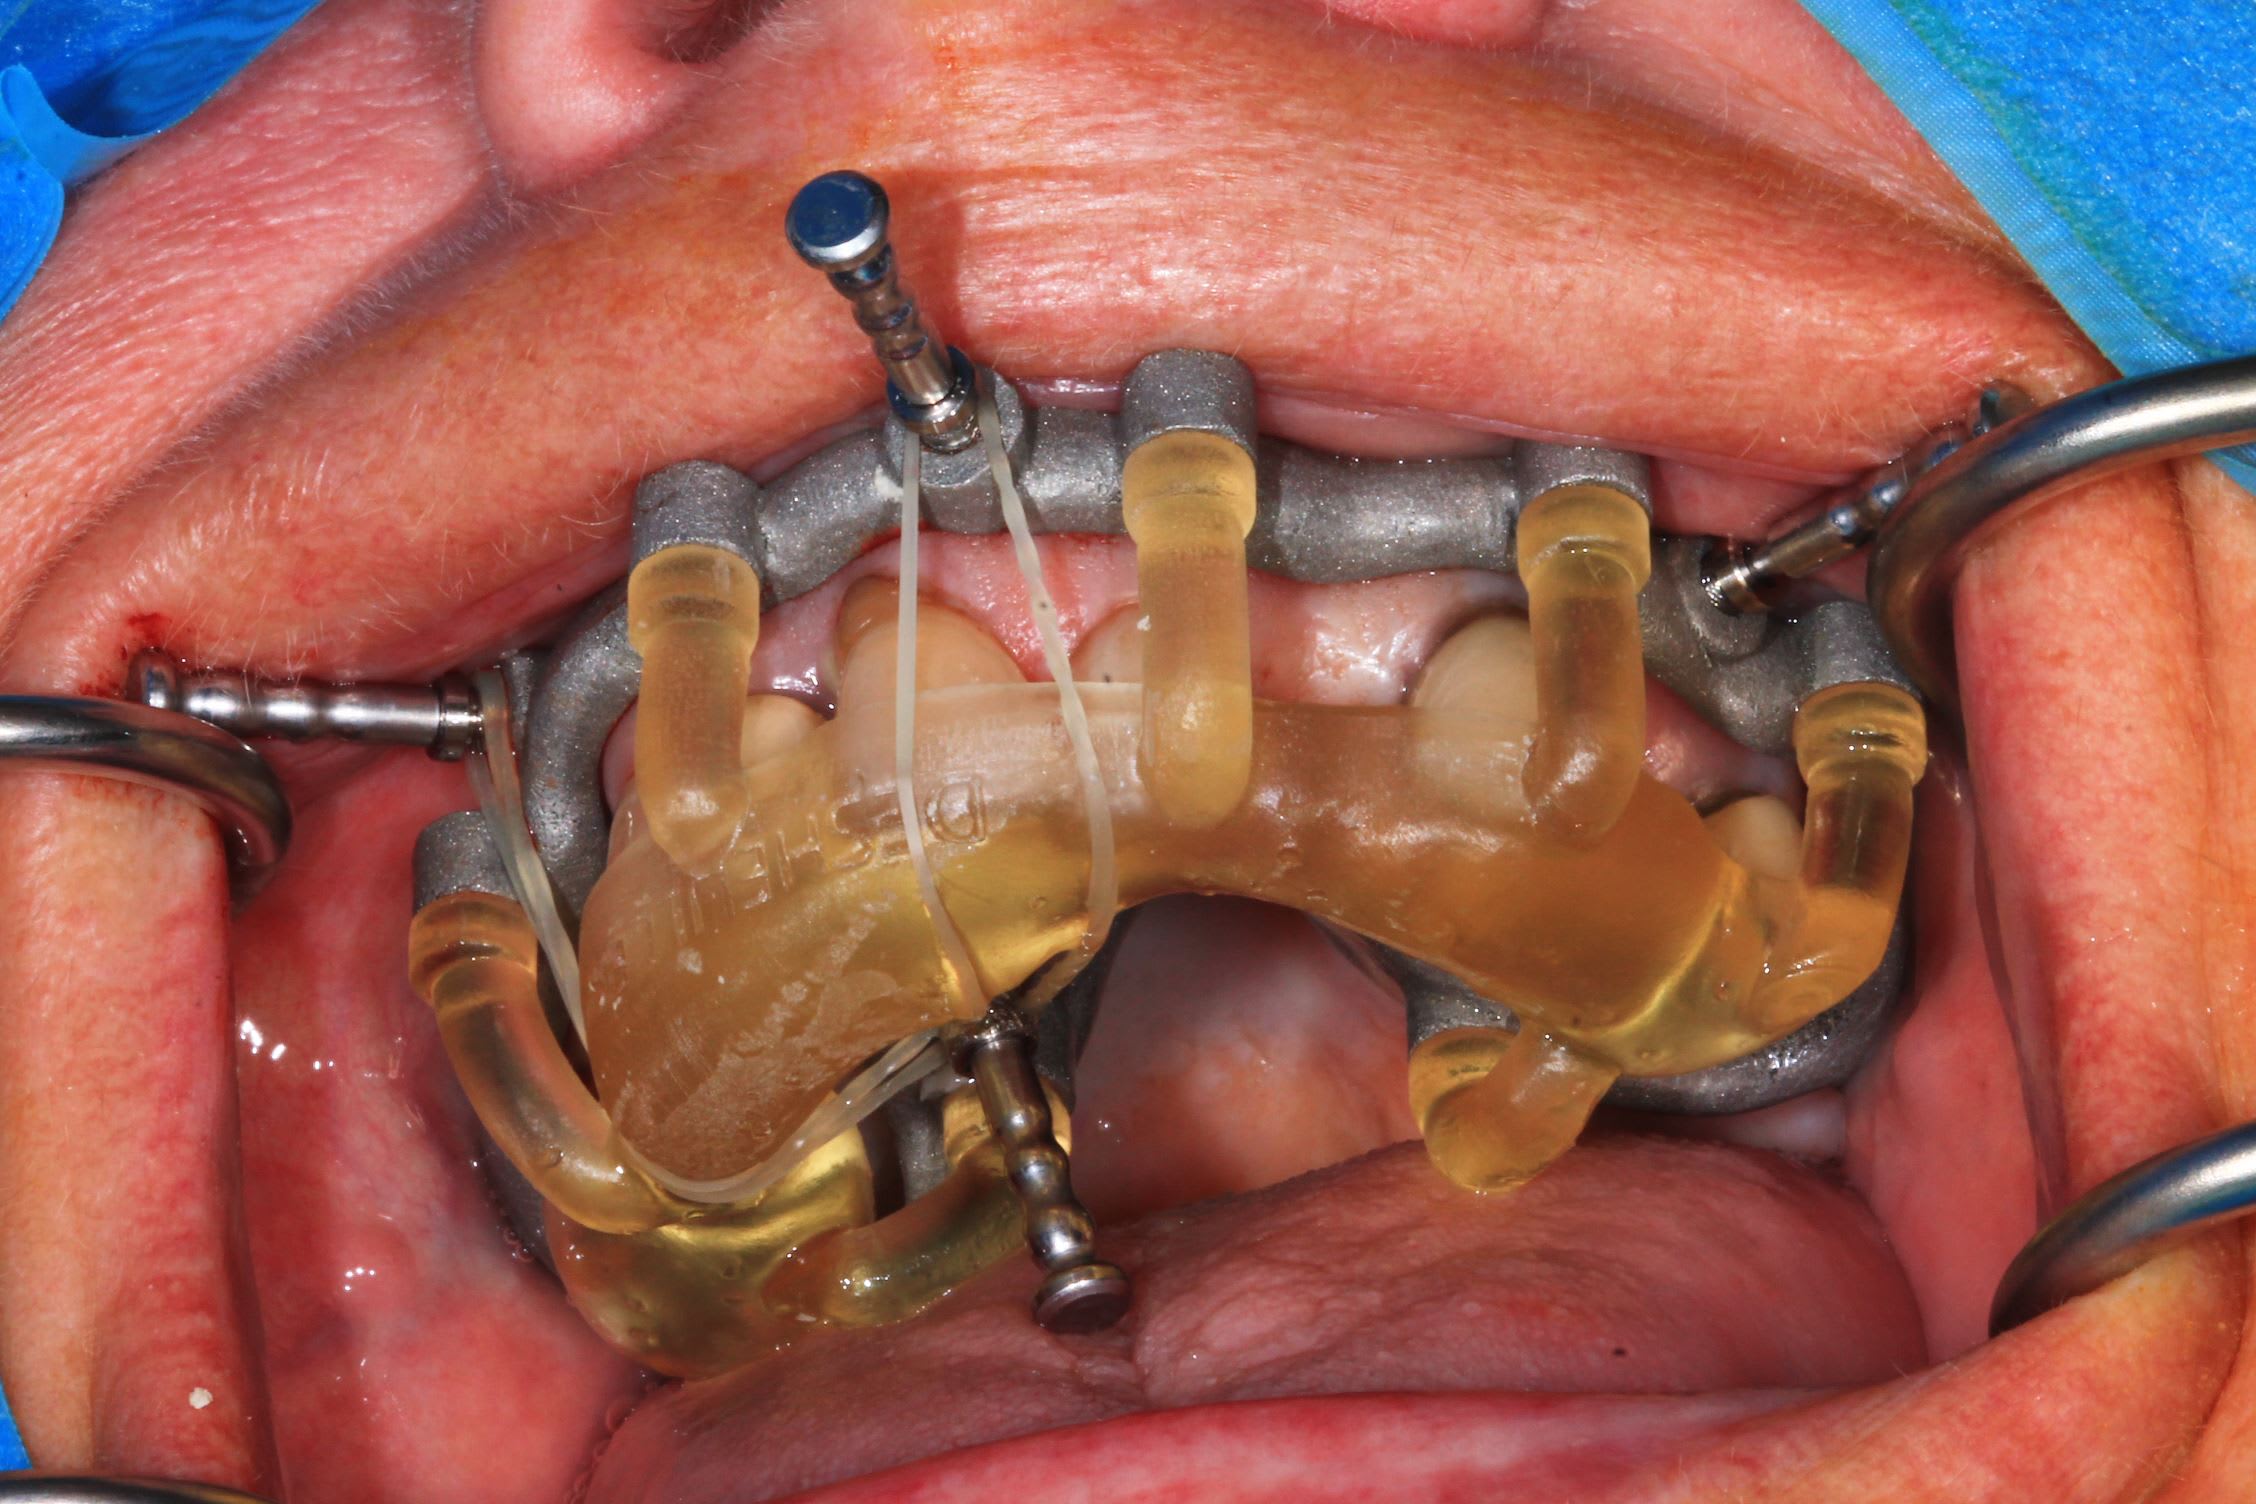

Ici : étage clavette positionné avec support dentaire, guide de forage full guided , trousse ETK, positionnement du bridge prov sur l’étage clavette , bridge avec armature métal et pilier collés en bouche.

Le cas de la semaine derniere : implants super stable. Premier coup de bistouri a 9h45, patiente sortie à 13h. J'ai galéré avec un satané apex cassé et des canines rebelles : presque 3/4 h pour les extractions !

la suite. Photo post op immédiate et a trois jours.